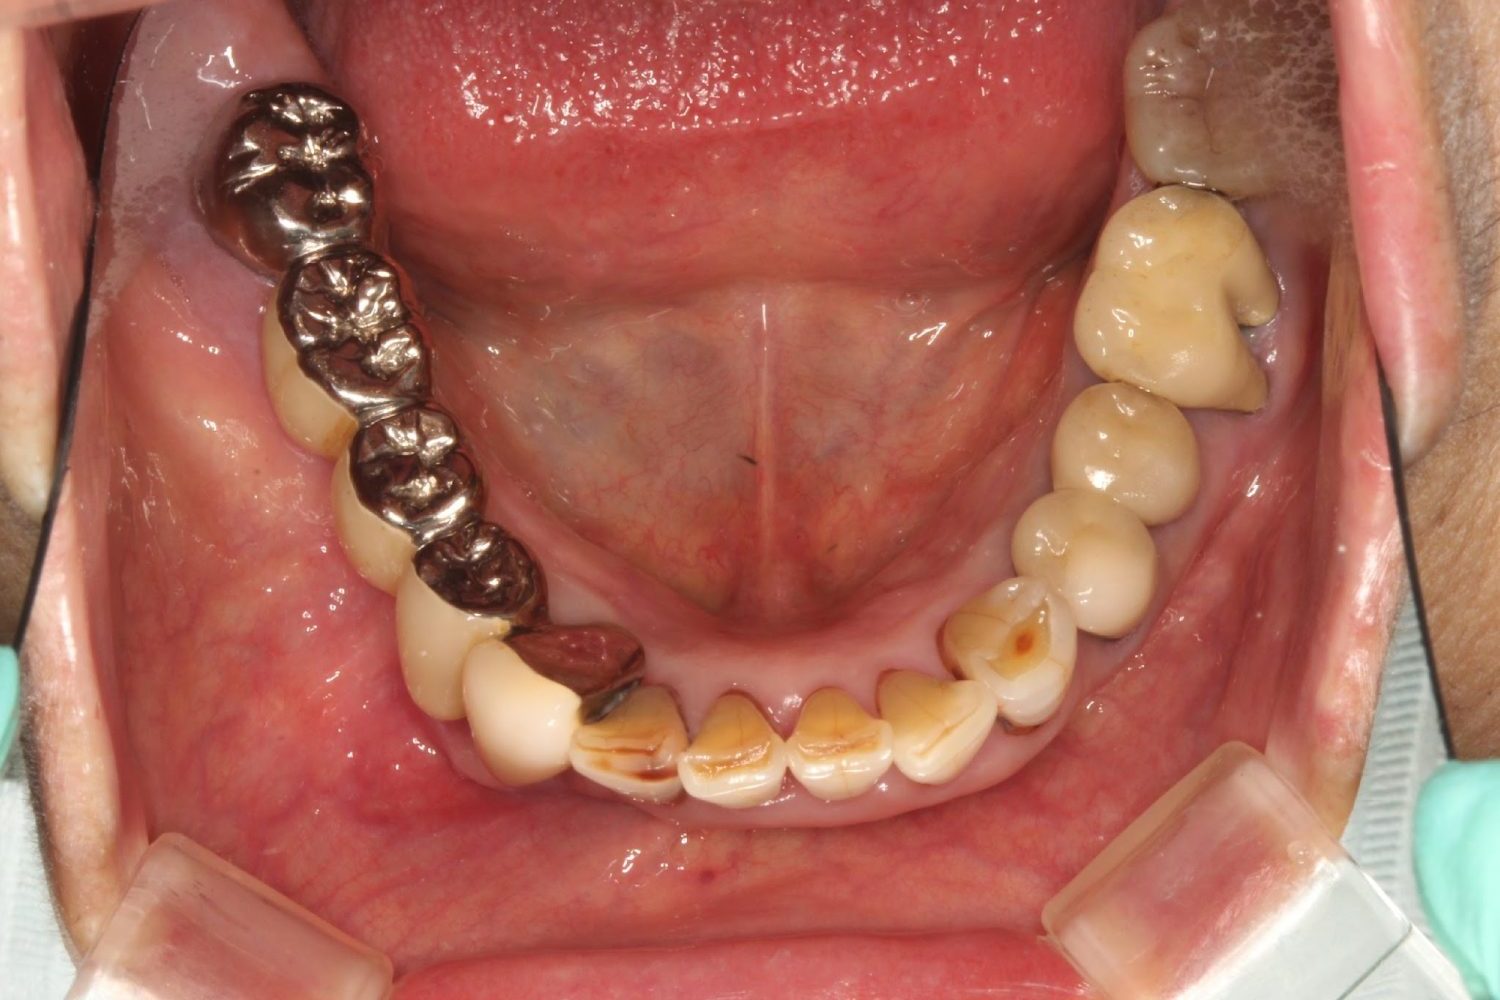

インプラント治療の症例紹介⑦

Before

治療中

After

主訴

歯肉の腫脹、安定した入れ歯を入れたい

治療内容

上顎に5本インプラント埋入を行いIOD。下顎は固定性を希望したので3本埋入し上部構造を装着しました。

治療費

3,377,000 円(税込)

治療期間

21ヶ月

通院回数

27回

想定されたリスク

※義歯を安定させるためのインプラントなので、顎堤が吸収等起こし裏装が必要になる可能性がありました。

濱 仁隆先生

浜歯科

上顎をロケーターアタッチメントにより義歯を安定させる事を可能にし、コストも下げられた症例。